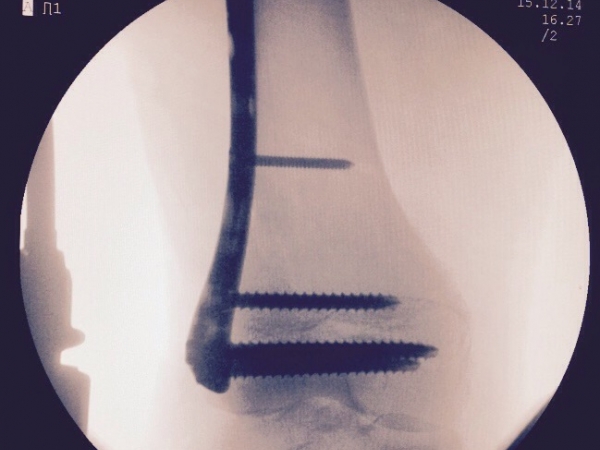

Images Gallery